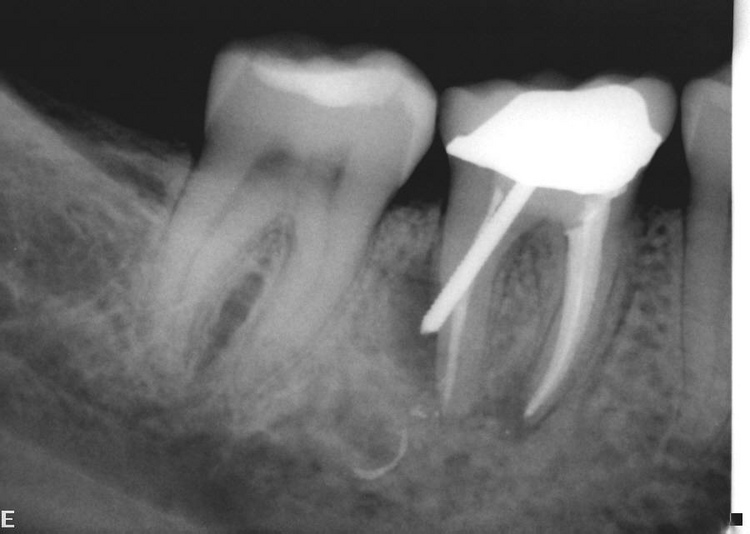

Tooth 13 after endodontic surgery with Er YAG laser. Download Laser Endodontic Surgery Soft tissue lasers such as co 2, diode and nd:yag are used to obtain clean incision for direct access to the periapical. Lasers stimulate atoms or molecules in order to emit a specific wavelength of light and amplify it, resulting in coherent, monochromatic, well. The purpose of this paper is to summarize laser applications in endodontics, including their use in. Laser Endodontic Surgery.